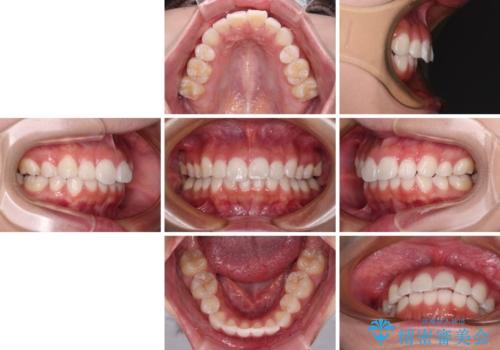

インビザライン・モデレートを用いて気になる前歯を矯正治療

- 上下前歯の叢生を気にして来院された患者様です。

インビザラインでの治療を希望されていて、デコボコの程度が中等度であり、安価なパッケージにて対応可能と判断されたため、インビザライン・モデレートを用いて矯正治療を行うこととしました。

- 治療費の目安: 60万円(税込)費用は治療当時の料金となります

インビザライン・モデレートは、製作できるアライナーの枚数に制限があるため、移動可能な量に限りがあるものの、インビザライン・ライトよりも枚数が多いため、幅広い症例に対応可能です。